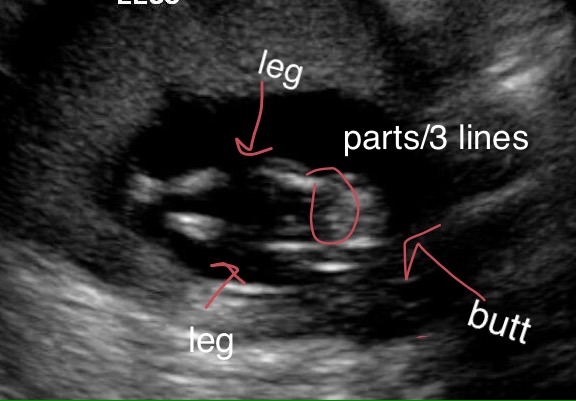

14 weeks girl or boy?

Here is the only 'potty shot' I got at my scan yesterday. It looks VERY similar to my daughters at 15 weeks and I see the three lines but I just need other eyes. The tech wouldn't even attempt to get a good look between the legs. Any guesses or too hard to tell?

It's a little hard to tell but I'll go with a very slight girl lean just because I see something protruding out...it could be swollen girl parts or a penis...just a little bit too hard to tell!

50/50 shot. You've got some cord in the way. I see the parts but not clearly enough.